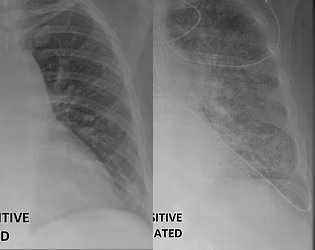

백신 접종한 코로나19 확진자의 폐(왼쪽)와 비접종 확진자의 폐(오른쪽)가 보인 엑스레이(X-Ray). 미국 방송국 KDSK

깨끗한 모습을 보인 백신 접종한 환자의 폐(왼쪽)에 비해 뿌옇게 나타난 비접종 환자(오른쪽)의 폐. 미국 방송국 KDSK

카멜 박사는 현지 언론과의 인터뷰에서 “백신이 만들어내는 차이를 보여주기 위해 이 엑스레이 사진들을 공개했다”며 “백신 접종을 하지 않은 코로나19 환자는 약물치료와 인공호흡기, 호흡을 위한 삽관 등 생명유지 장치를 필요로 할 수 있다”고 설명했다.